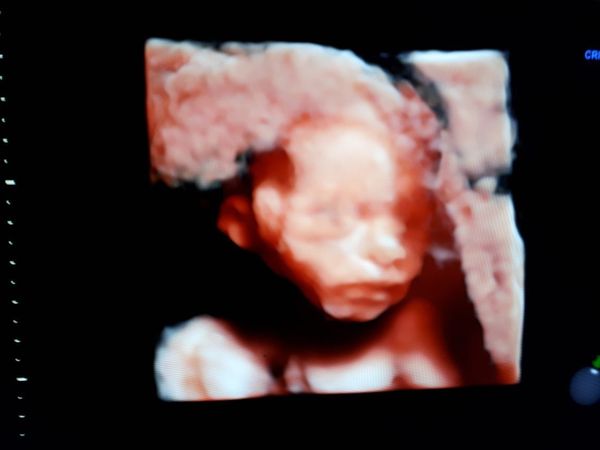

Mummyloves09 · 29/01/2018 23:15

I had my 20 week scan today all was well. The little jelly bean was really active so it was really difficult to catch her properly taking 1 hour and 30mins to scan. The sonographer was extremely lovely and done a 3d image of her face which melted my heart even more.